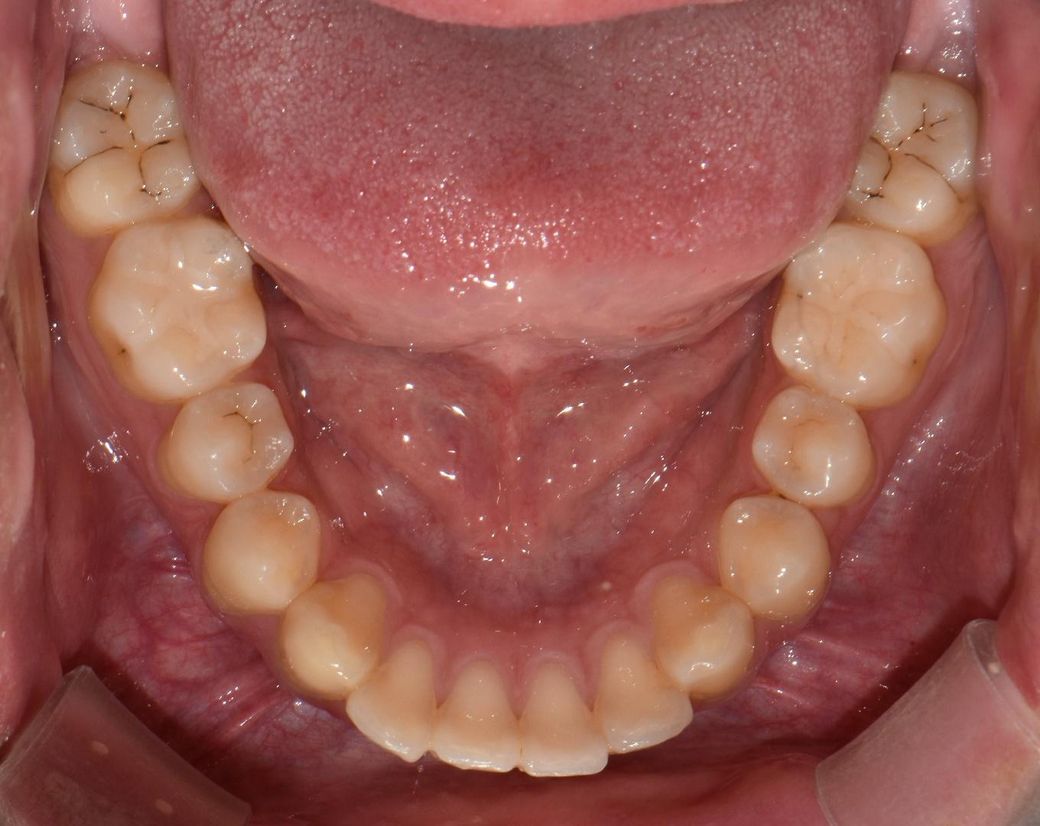

사진속 충치가 다시 번지면 인레이인가요?

사진속 구강상태에서 초기 정지우식이라고합니다. 근데 재광화가풀려 며칠동안 조금이라도 정지우식이 다시 진행되었다면, 진행된지 고작 2주정도 지났다고 쳐도 인레이가 필요한치아가 있나요? 많이 진행되지않고 2주동안 이제막 충치가번지기 시작하는경우, 레진인지 인레이인지 궁금합니다

이정도면 초기상태 충치가 맞고 여기서 좀 더 진행되더라도 인레이까지는 안갈 것 같습니다.

충치가 진행이 되는 것이 치아 사이의 경우에는 보통 레진보다는 인레이로 치료하는 것이 일반적입니다.

충치의 범위가 넓거나 인접면에 충치가 있는 경우에는 보철치료를 하게 됩니다.

범위가 넓지 않다면 인레이 치료를 할수 있지만 범위가 넓다면 크라운 치료가 필요할 수 있습니다.